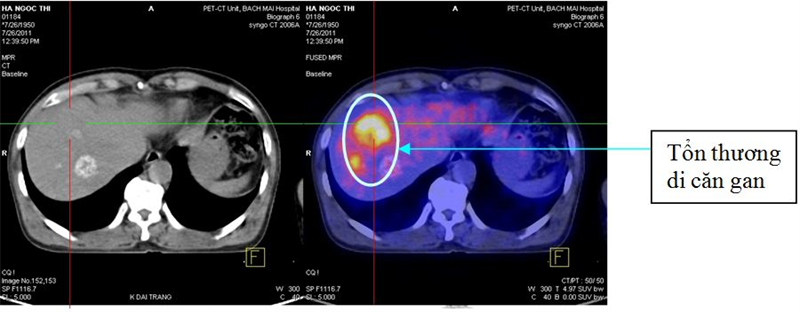

Một số hình ảnh minh họa:

Tổn thương di căn gan đa ổ

PET/CT phát hiện được 18 bệnh nhân có tổn thương di căn phổi, 14 bệnh nhân có tổn thương di căn gan: 6 trường hợp di căn gan phải, 2 trường hợp di căn gan trái và 6 trường hợp di căn đa ổ cả gan phải và gan trái. Các tổn thương di căn xương chủ yếu là xương cột sống, xương đùi. Không có bệnh nhân nào có tổn thương di căn não.10 bệnh nhân có các ổ tổn thương di căn thành bụng từ 1 đến 2 ổ, với. 3 bệnh nhân có tổn thương di căn mạc treo ổ bụng. 1 bệnh nhân có tổn thương tại hạ họng; 1 bệnh nhân có tổn thương tại tuyến giáp.2 bệnh nhân có tổn thương ở tụy. 1 bệnh nhân có di căn âm đạo; bệnh nhân này sau đó đã được phẫu thuật cắt bỏ tổn thương di căn âm đạo và điều trị hóa xạ trị; bệnh nhân này được làm PET/CT đánh giá lại sau điều trị: tổn thương tại âm đạo đã tan hết nhưng lại xuất hiện thêm mới là 2 hạch chậu, đường kính 1,2cm và 1,7cm, tăng hấp thu F-18 FDG, max SUV=4,86 và 5,18.